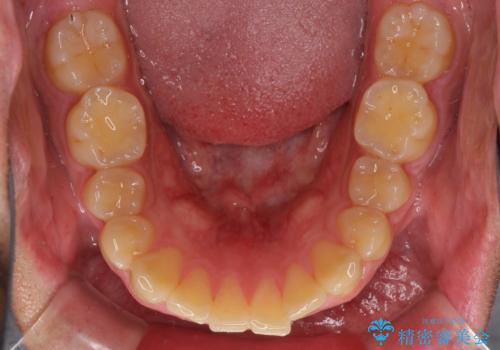

- 前歯のデコボコを気にして来院された患者様です。

当院でインビザライン矯正治療をされている方からのご紹介ということで、インビザラインでの矯正治療をご希望でした。

ワイヤー矯正に比べ来院頻度は低いものの、新幹線での通院のため、やや治療期間が延びることが懸念されました。